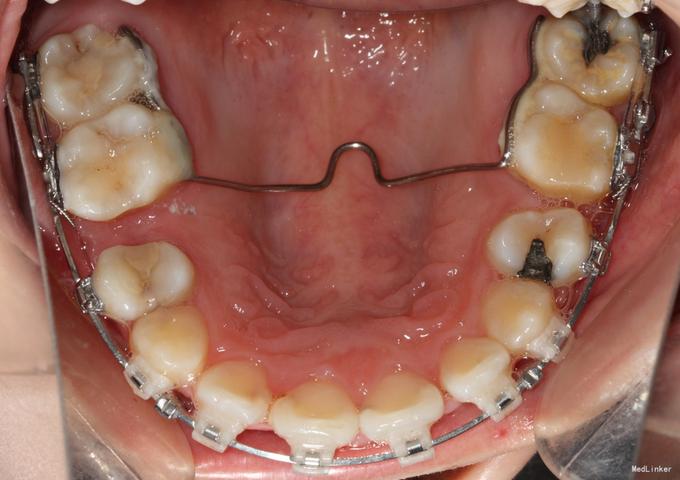

TPA的核心结构由连接体和两个臂部组成,连接体跨越腭中缝,位于硬腭黏膜上方,两个臂部则通过焊接或整体弯制的方式,与后牙的带环或托槽连接,根据临床需求,TPA可分为多种类型,其设计差异主要体现在形态、材质和连接方式上,具体如下表所示:

(图片来源网络,侵删)